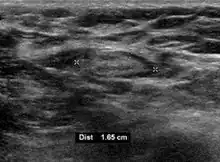

- Absence of the fatty hilum

- Increased focal cortical thickness greater than 3 cm

- Doppler ultrasonography that shows hyperaemic blood flow in the hilum and central cortex and/or abnormal (non-hilar cortical) blood flow.[26]

On ultrasound, B-mode imaging depicts lymph node morphology, whilst power Doppler can assess the vascular pattern.[28] B-mode imaging features that can distinguish metastasis and lymphoma include size, shape, calcification, loss of hilar architecture, as well as intranodal necrosis.[28] Soft tissue edema and nodal matting on B-mode imaging suggests tuberculous cervical lymphadenitis or previous radiation therapy.[28] Serial monitoring of nodal size and vascularity are useful in assessing treatment response.[28]